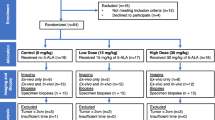

We conducted an IRB-approved, prospective, non-randomized, open-label study at Massachusetts General Hospital, Boston, MA. Eligibility included age > 18 years, invasive breast cancer and/or DCIS and a plan for lumpectomy. Patients with prior ipsilateral cancer surgery, open surgical biopsy for diagnosis or neoadjuvant systemic therapy were excluded.

Forty-five breast cancer patients received intravenous LUM015 at 1.0 mg/kg 56–402 min prior to surgery. Median age was 59 years (range 44–79) with 14 (31%) premenopausal or perimenopausal and 31 (69%) postmenopausal. Thirty-five patients required wire or seed localization for excision of non-palpable tumors. Mean tumor size was 1.2 cm (range 0.06–3.5 cm). Tumor histology included 25 (55%) invasive ductal carcinomas ± DCIS, 5 (11%) invasive lobular carcinomas, 3 (7%) invasive carcinomas with ductal and lobular features, and 12 (27%) DCIS only (Table 1). Breast density on mammography was heterogeneously or extremely dense in 24 (54%), fatty or scattered fibroglandular densities in 19 (42%) and mixed dense and scattered density in 2 (4%).

The minimum acceptable timepoint to begin imaging after injection of LUM015 was determined by finding the shortest timepoint at which the detection algorithm successfully predicted the presence of tumor. The lower bound for the imaging timepoint was 101 min. Two patients were excluded from the analysis because the imaging timepoint was less than 101 min (56 and 92 min). The longest time between injection and imaging in the study was 402 min, and the signal remained acceptable at this timepoint.

Five patients’ data were not used in development of the tumor detection algorithm. In 2 patients, cavities were imaged at less than the 101-min minimum interval between LUM015 injection and imaging; 1 patient did not receive the planned LUM015 dose due to extravasation of LUM015 into surrounding tissue during injection; 1 tumor cavity had extensive necrotic tissue and hematoma at the core biopsy site with limited fluorescent signal; and 1 patient’s intraoperative imaging data was lost before analysis. This left 40 patients whose data was used for algorithm development. Safety assessments were performed on all 45 patients who received LUM015 injections.